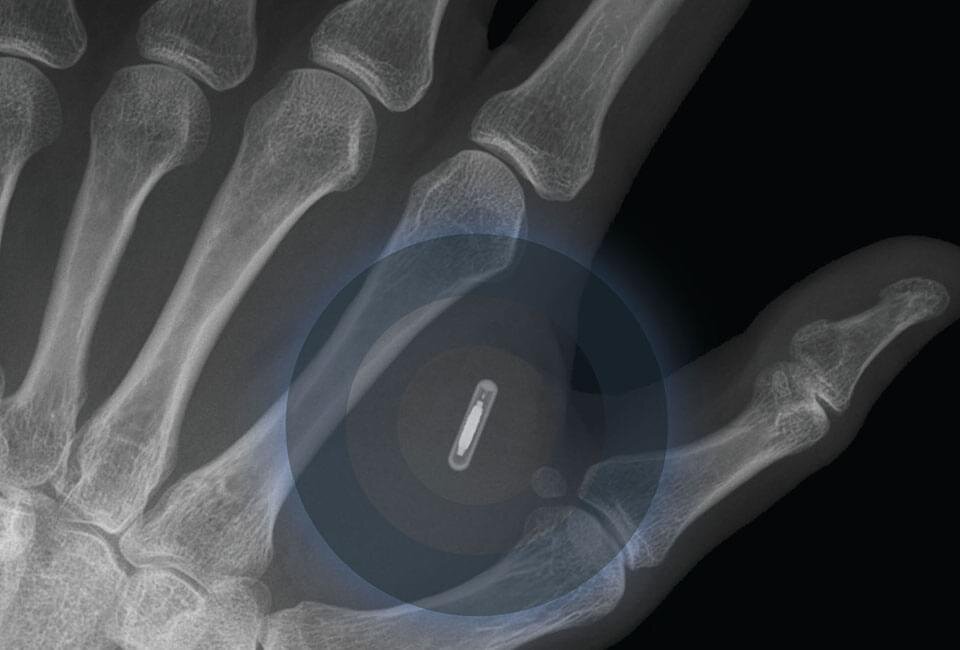

Die Trainingszentren der Topclubs gleichen mittlerweile NASA-Forschungslaboratorien. Es wird gemessen, ausgewertet, Daten erfasst, analysiert und in die Trainingssteuerung einbezogen. Es ist mittlerweile Standard, dass die körperlichen und sportlichen Parameter systematisch erfasst und ausgewertet werden. Spieler werden bereits heutzutage in den Bereichen Spiel, Training, Ernährung, Schlaf und Geist dauerhaft begleitet. Dabei wurde festgestellt, dass in den Bereichen ‚Schlaf’ und ‚Geist’ am meisten Potential steckt. Es ist vorstellbar, dass schon 2020 smarte Nano-Implantate eingesetzt werden, um umfangreiche Informationen in Echtzeit liefern zu können. Die Möglichkeiten liegen dabei durchaus auf der Hand, beziehungsweise in der Hand. Den Spielern ist es nämlich nicht erlaubt Fitnesstracker während des Spiels zu tragen, jedoch könnte ein implantierter Nanochip dieses Problem lösen und alle Leistungsdaten sammeln.